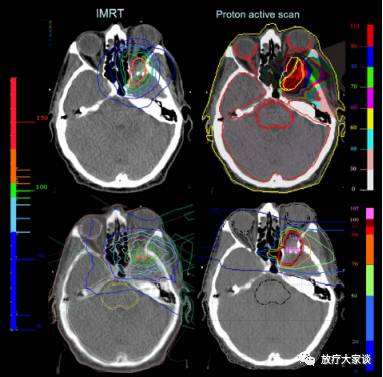

4.12.2  计划对比

放疗计划系统有哪些放射治疗计划系统(TPS)介绍_https://www.jmylbn.com_新闻资讯_第13张